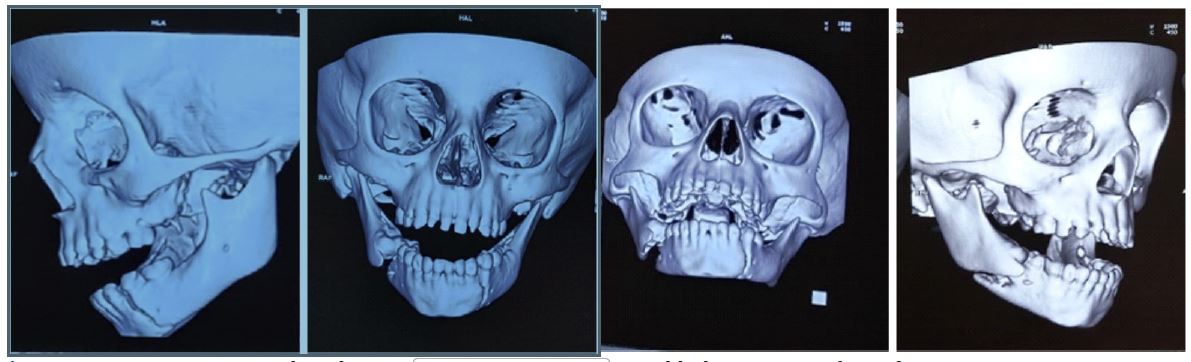

The provisional diagnosis was a combined fracture of the left para symphysis associated with a right mandibular body, and Cone beam computed tomography (CBCT) was suggested to confirm it. The Orthopantogram (OPG) and Cone beam computed tomography (CBCT) preoperatively confirmed left para symphysis fracture with a step at the inferior border of the mandible. An associated minimally displaced fracture was present on the right mandibular body region (Figures 2,3). Routine hematological investigations were advised, and emergency treatment was started. Meanwhile, antibiotics and analgesics were prescribed, along with a dose of tetanus toxoid injection. Intravenous fluids were also prescribed since the child was unable to take food orally.

Figure 3: CBCT 3D view reveals right mandibular body and left mandibular para symphysis fracture.